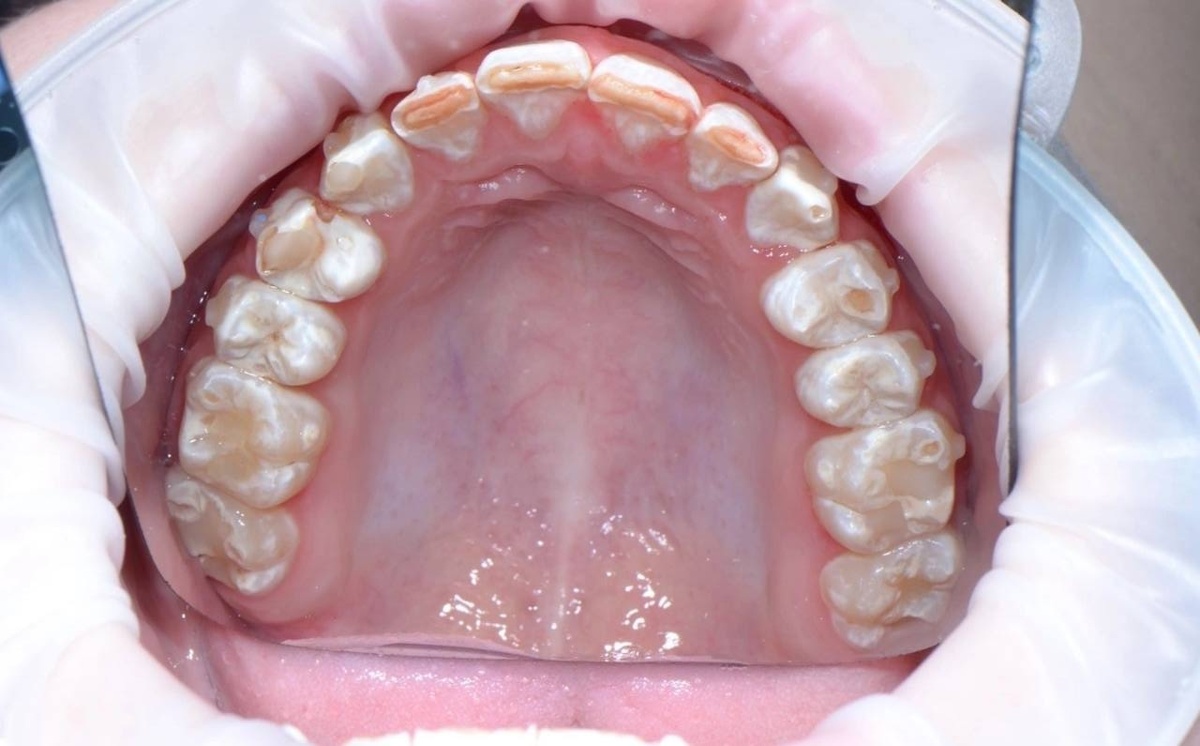

Эрозии на нёбной поверхности зубов верхней челюсти, на жевательной поверхности - можно предположить, что причина в хронической рвоте или в забросе кислого содержимого желудка в полость рта.

Небные и окклюзионные поверхности - эрозии. Признак внутренних причин появления эрозий